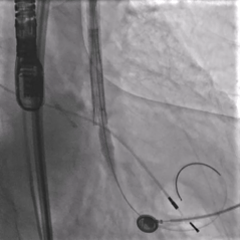

大弯侧0位,形态可见压缩

小弯侧深度尚可

瓣膜脱钩,轻微自同轴

脱钩后造影,瓣膜稳定,无反流

左侧位造影,小弯侧深度尚可